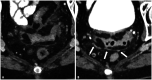

Photon-counting detector (PCD) CT is a new CT technology utilizing a direct conversion X-ray detector, where incident X-ray photon energies are directly recorded as electronical signals. The design of the photon-counting detector itself facilitates improvements in spatial resolution (via smaller detector pixel design) and iodine signal (via count weighting) while still permitting multi-energy imaging. PCD-CT can eliminate electronic noise and reduce artifacts due to the use of energy thresholds. Improved dose efficiency is important for low dose CT and pediatric imaging. The ultra-high spatial resolution of PCD-CT design permits lower dose scanning for all body regions and is particularly helpful in identifying important imaging findings in thoracic and musculoskeletal CT. Improved iodine signal may be helpful for low contrast tasks in abdominal imaging. Virtual monoenergetic images and material classification will assist with numerous diagnostic tasks in abdominal, musculoskeletal, and cardiovascular imaging. Dual-source PCD-CT permits multi-energy CT images of the heart and coronary arteries at high temporal resolution. In this special review article, we review the clinical benefits of this technology across a wide variety of radiological subspecialties.